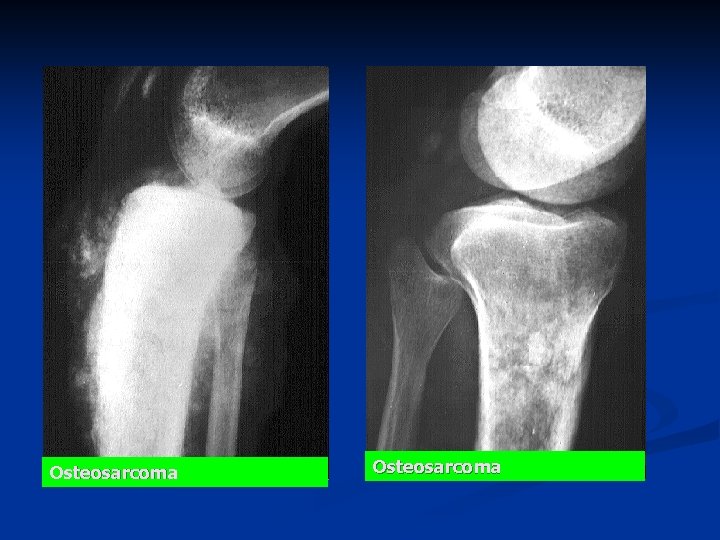

n n n Radiology of a long bone usually show a large, ill-defined tumor. The bone-producing (osteoblastic) lesion is located in the medulla near the metaphysis Lifts up the periosteum (periostal reaction) n n n often producing "Codman's triangle", an angle between the outer cortex and the elevated periosteum, Sun-rays pattern Less common : n destructive (osteolytic) lesions with a "moth eaten" appearance of the cortex.

Osteosarcoma

Osteosarcoma